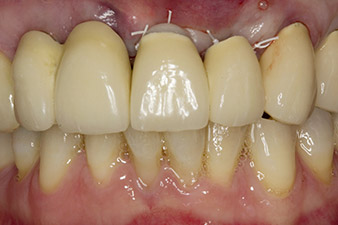

When the patient first presented, teeth 21, 22 and 23 had been restored with splinted crowns, now 19 years old, which were bonded to the implants at positions 12/11 by an attachment (cf. Fig. 2).

Tooth 23 displayed a horizontal-coronal fracture and was restored with a post and core build-up for the temporary restoration. The plan was to place a zirconium oxide bridge on the existing implants at positions 12 and 11 and to place two new implants at positions 22 and 23.

Following primary healing, the soft tissues were shaped using the basally lined bridge. Two months later the site was exposed by a slightly palatal alveolar ridge incision (Fig 2). The dimensions of the alveolar bone proved to be sufficient at position 22. Figures 2 and 4 show the preparation of the implant bed, the tapping and the implantation using Implantmed.

In this case study, the situation was resolved with an implant at position 22 in the first procedure and an additional one at the position of the extracted tooth 23 later in the course of the treatment. The second implant was inserted following successful osseointegration of implant 22. The revised bridge was reinserted until implant 23 healed in place and the shaping for the permanent restoration was complete. The advantages of this gradual approach include the implants’ being able to accept loads more resiliently and mature hard and soft tissues (5).